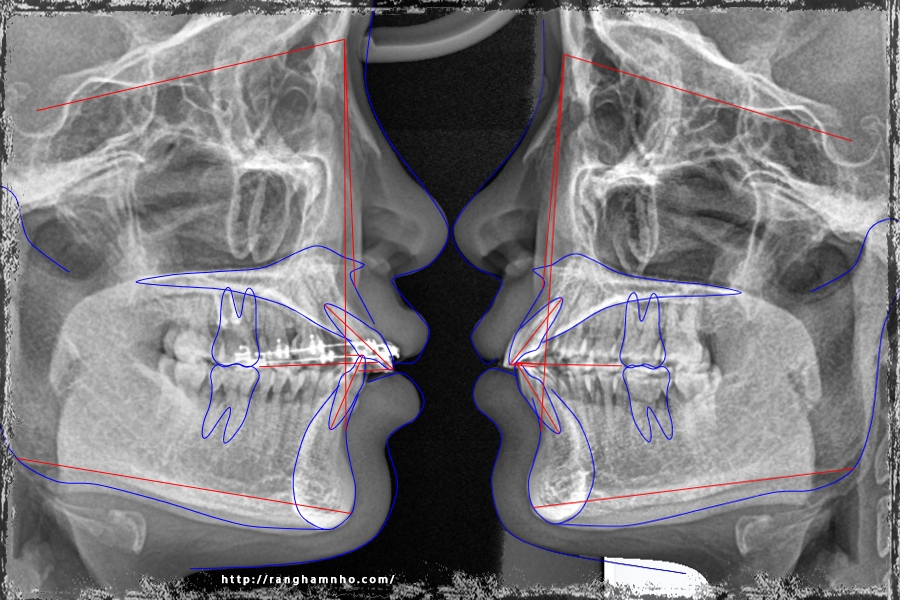

Phim chụp so sánh kết quả trước điều trị và kết quả sau điều trị.